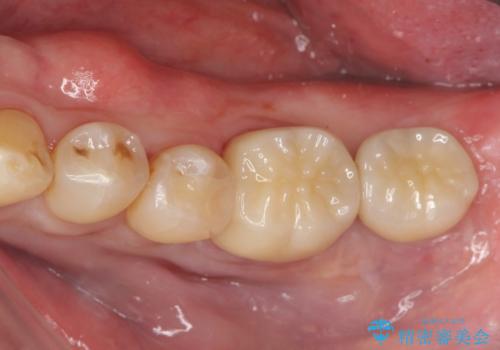

咬合平面を揃え、早期接触・干渉を防ぐ補綴治療

咬合の調和、均等に力がかかることでより長期的な予後を期待することができます。

今回、左下6は頬側歯頚部に虫歯があり圧下を行ったことからクラウンにより補綴を行いました。